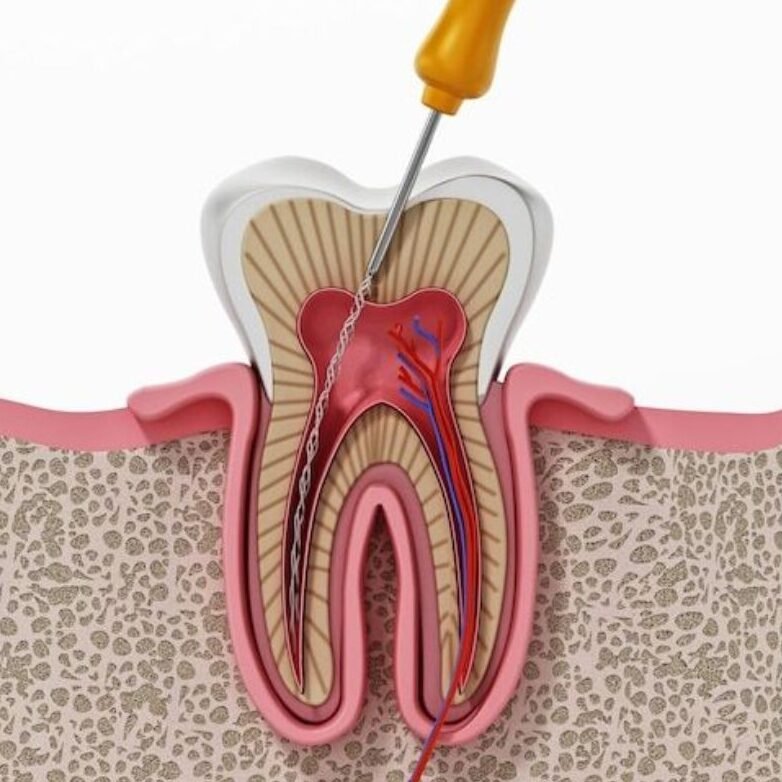

Perawatan saluran akar untuk mengatasi infeksi pada jaringan gigi bagian dalam, menjaga gigi tetap sehat.